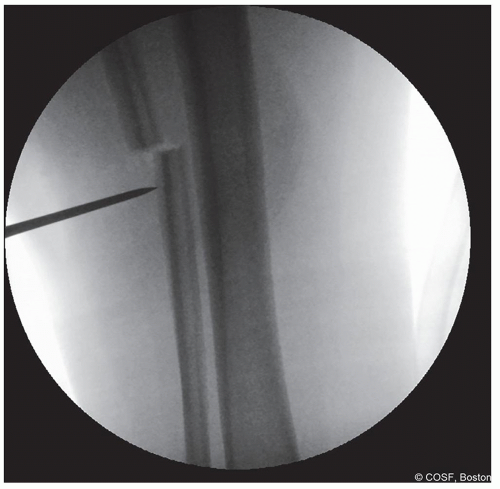

A 2.5 mm drill is utilized to make a series of drill holes laterally, which are fanned in the appropriate plane posteriorly, anteriorly, and medially

An osteotome is utilized to complete the cut

Mobility of the proximal and distal fragments must be confirmed by visualizing translation under fluoroscopy (Figure 25.4)